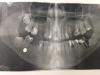

diesel87 Опубликовано 11 ноября, 2013 Поделиться Опубликовано 11 ноября, 2013 Снимки с разницей в 8 месяцев Пациент помимо удаления зубов, попросил извлечь пулю, ей уже 40 лет) 1 Ссылка на комментарий

diesel87 Опубликовано 11 ноября, 2013 Автор Поделиться Опубликовано 11 ноября, 2013 дробинка что ли? Чего то она не деформировалась? В мягких тканях лежит?Да, больше в мягких Ссылка на комментарий

diesel87 Опубликовано 11 ноября, 2013 Автор Поделиться Опубликовано 11 ноября, 2013 Первый снимок сделан 8 мес назад, последнюю неделю зуб начал сильно беспокоиться, со слов пациентки, сегодня фото делаем и "о чудеса"))) 1 Ссылка на комментарий

diesel87 Опубликовано 11 ноября, 2013 Автор Поделиться Опубликовано 11 ноября, 2013 Меня больше поразил повернувшийся дистопировано-ретенированный 37 зуб)) Ссылка на комментарий

АнтонТЛТ Опубликовано 11 ноября, 2013 Поделиться Опубликовано 11 ноября, 2013 Меня больше поразил повернувшийся дистопировано-ретенированный 37 зуб))Если обратить на бугры 7-ки, то можно заметить, что второй снимок сделан в перпендикулярной к продольной оси зуба. А первый снимок под очень большим углом. Так что если 8-ка повернулась, то минимально. Думаю, что там никакого поворота не было Ссылка на комментарий

diesel87 Опубликовано 11 ноября, 2013 Автор Поделиться Опубликовано 11 ноября, 2013 Да, скорее всего проекция немного другая, судя по изменению 36 зуба, но в полости рта 37 все таки поменял свое положение, причем не минимально Ссылка на комментарий